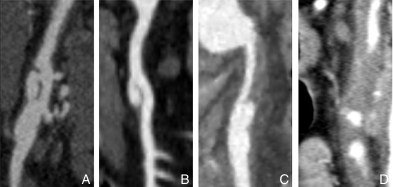

图2 腔内介入 A:支架植入;B:支架植入+弹簧圈假腔栓塞Fig.2 Endovascular intervention A: Stent implant-ation; B: Stent implantation with coil embolization of the false lumen